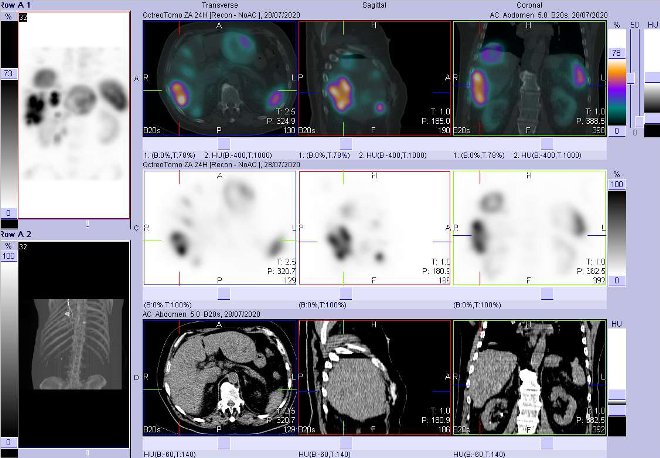

Pomocí dvoudetektorové hybridní tomografické kamery Symbia T2 (SPECT/CT) firmy Siemens opatřené kolimátory pro střední energie jsme provedli celotělovou scintigrafii a také cílenou tomografickou scintigrafii (SPECT) a CT a fúzi obrazů SPECT/CT hrudníku, břicha a pánve za 4 hod. a 24 hod.

(obr. 1-7) po i.v. podání 190 MBq analogu somatostatinu značeného

111In (přípravek OctreoScan firmy Mallinckrodt Medical).

/ Obr. č. 7: Fúze obrazů SPECT a CT – vyšetření 24 hod. po aplikaci radiofarmaka. Zaměřeno na ložisko v dorzolaterální části pravého jaterního laloku.

/

Závěr: mnohočetná patologická ložiska se zvýšenou denzitou somatostatinových receptorů v játrech (největší v levém laloku s centrálním rozpadem velikosti až 10 cm), uzlinách periportálně, retroperitoneálně suprarenálně, na mezenteriu. Zřejmě nespecifický nález v blízkosti levého akromioklavikulárního skloubení spíše zánětlivého původu.